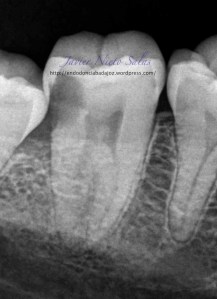

Se le volvió a citar a la paciente al mes, para reevaluar el caso.

Desaparece el sondaje patológico y la fistula.